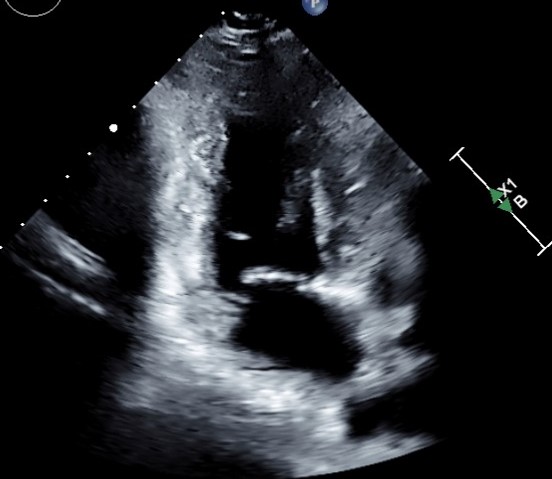

Image- Echocardiogram (various apical views)